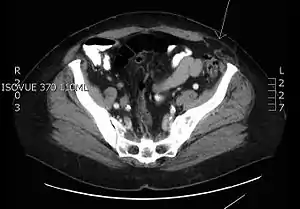

Transverse CT image of the abdomen in a patient with a Spigelian hernia (arrow).